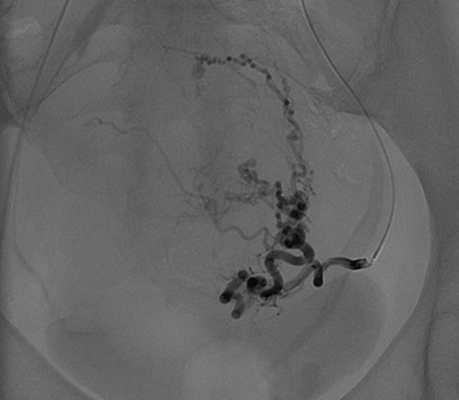

Bei der Uterus-Embolisation handelt es sich um ein Behandlungsverfahren, bei welchem die Gefäße, welche die Myome versorgen, unter röntgenologischer Kontrolle (teil)verschlossen werden.

Vor einer geplanten angiographischen Intervention wird zunächst zur besseren anatomischen Übersicht eine diagnostische Magnetresonanztomographie des kleinen Beckens inklusive einer Gefäßdarstellung durchgeführt. Im Rahmen des eigentlichen Eingriffes wird ein Katheter im zuführenden Gefäßsystem des Myoms platziert. Über diesen Katheter wird das zuführende Gefäßsystem embolisiert (verschlossen). Dies kann durch eine langsame Gabe von Kunststoff-Kügelchen oder auch Polyvinylalkohol (PVA) geschehen. Die kleinen Partikel fließen in die Endarterien des Myoms und verbleiben darin. Über mehrere Minuten werden die zuführenden Gefäße so blockiert. Dies führt zu einem Absterben des Gewebes im Myom und nachfolgend zu einer Verkleinerung und Symptomlinderung.